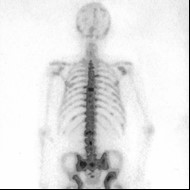

Przedstawiony obraz został zarejestrowany podczas wykonywania

Ilustracja do pytania 15

A. tomografii komputerowej.

B. rezonansu magnetycznego.

C. pozytonowej tomografii emisyjnej.

D. badania radioizotopowego.